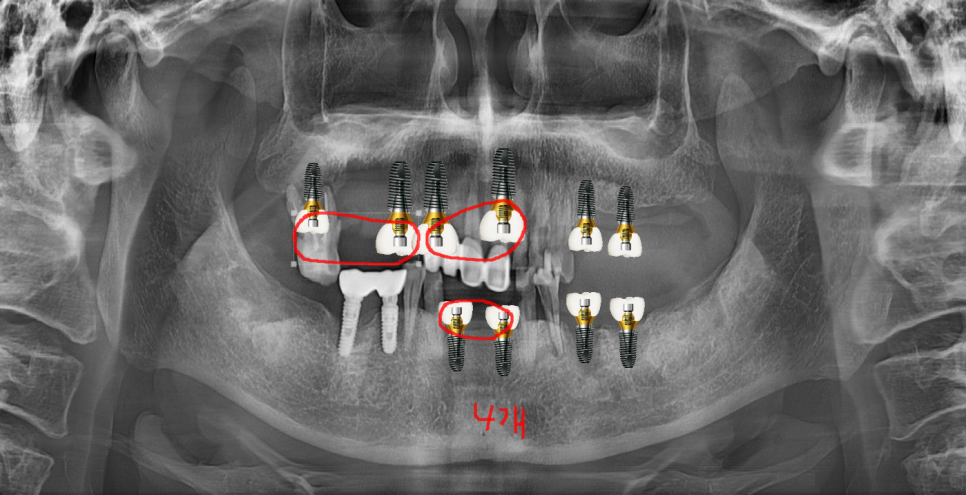

231104

수술을 하고보니 눈에 띄는 충치...

다같이 치료하면 좋을텐데

아쉬움이 남지만

환자분 상황도 고려해야하니까..

240120